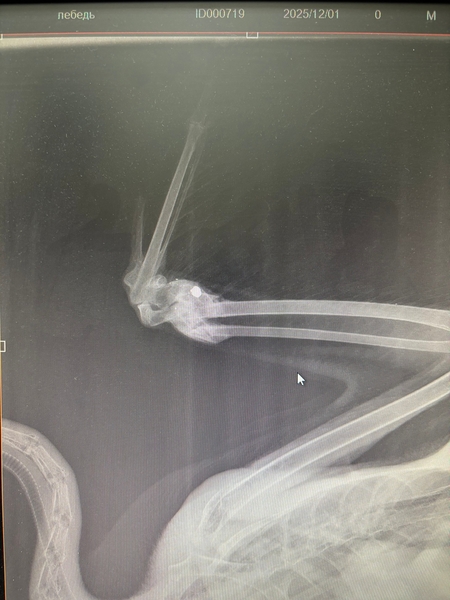

После клинического осмотра и рентгенографии ветеринарные врачи диагностировали у неё мелкооскольчатый перелом локтевой и лучевой костей крыла. «Предположительно, лебедя подстрелили», – отметили в учреждении, добавив, что летать он уже не сможет.